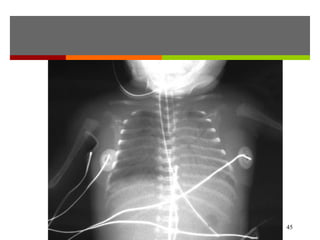

Chest x-rays: infiltrates or effusion

44

Chlamydia pneumonia with features of an interstitial

pneumonitis and characteristic widespread interstitial changes.